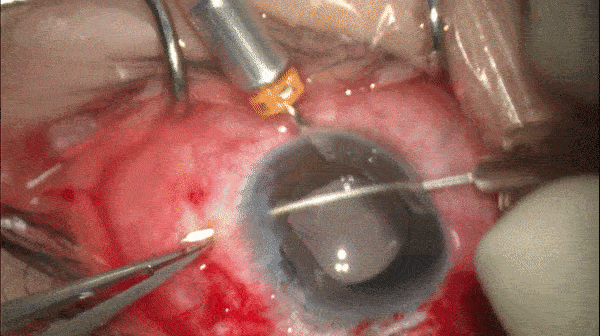

Step 9

固定结(fixation knot)和锚结(anchor knot)

在固定位置将双股缝线制成固定结,以固定缝线。

在距固定结2.0mm-3.0mm位置制作“2-1-1”交叉线结(锚结),以便于后续埋线。